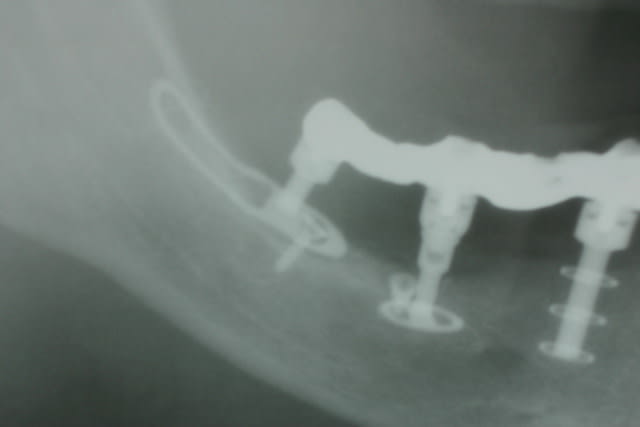

Tenez

voici les clichés de contrôle à 2 ans post op

Pépé

en échec les 2 cylindres: résorption osseuse? péri-implantite? autre chose? j'aperçois sur la radio des pins, il y a eu une ROG, pour que ces 2 cylindres ne soient plus problématiques?

il ne s'agit pas d'une marque qui propose des pièces intermédiaires pour transformer la connexion interne en hexagone externe succeptibles de rattraper le pb de parallélisme?

En échec non pas sur les implants mais sur la prothèse qui n apportait pas satidfaction..car les implants étaient ds des axes trop divergeants ( piège des crêtes étroites )

Les pins sont des vis d ostéosynthèse placées pour empêcher l intempestive langue de pousser sur les pileirs pdt les 48 h de fabrication des dents fixes

Aucune transfo nécessaire : vissage à plat comme on appelle cela